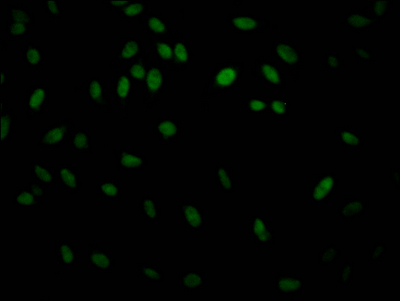

Immunofluorescence staining of Hela Cells with CSB-RA256500A0HU at 1:50, counter-stained with DAPI. The cells were fixed in 4% formaldehyde, permeated by 0.2% TritonX-100, and blocked in 10% normal Goat Serum. The cells were then incubated with the antibody overnight at 4℃. Nuclear DNA was labeled in blue with DAPI. The secondary antibody was FITC-conjugated AffiniPure Goat Anti-Rabbit IgG (H+L).